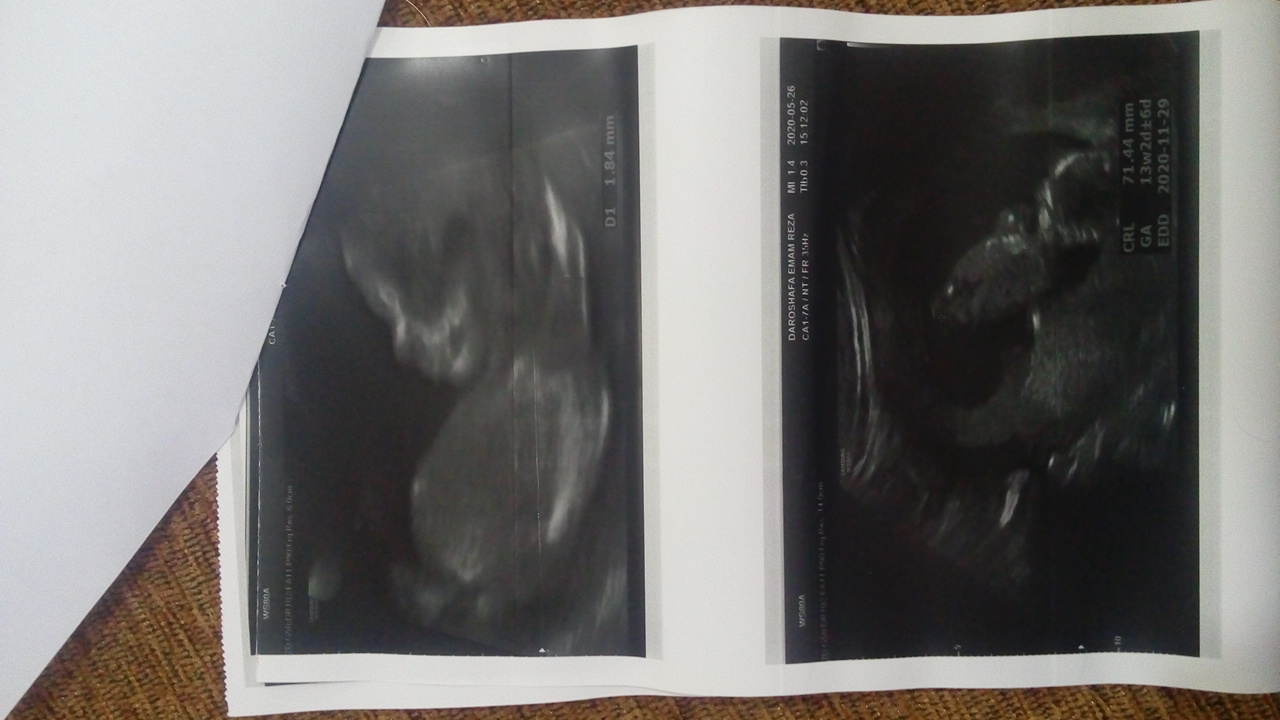

2500hadis مدیر استارتر عضویت: 1399/04/06 تعداد پست: 83 عنوان سونو ان تی😊😊😊😊😘❤ 842 بازدید | 64 پست سلللللام خانوما امروز رفتم سونو ان تی همه چی خوب بود خدارو شکر عدد ان تی 1.85 بود ان بی هم خوب بود جنسیتم گفت دختره😊👶💋😘فقط یه چیزی گفت جفتت خلفی پرویا هست باید استراحت کنی تا خوب بشه جفتم خطرناکه یعنی؟؟؟😑😥 1399/05/26 | 00:33 0 نفر لایک کرده اند ... گزارش تاپیک نامناسب

sinzed عضویت: 1399/05/11 تعداد پست: 2517 جنسیت رو دقیق گفت بهت عزیزم؟اگه دوست داشتی عکسشو بزار ببینم دقیق گفته یا ن😘 بیستون هیچ،دماوندم اگر سد بشود...هدفم قسمت من بوده و باید بشود✌🏻🍃 برای خوشبختی هممون یه صلوات بفرست :) 💜

2500hadis مدیر استارتر عضویت: 1399/04/06 تعداد پست: 83 جنسیت رو دقیق گفت بهت عزیزم؟ اگه دوست داشتی عکسشو بزار ببینم دقیق گفته یا ن😘 گفت احتمال زیاد دختره😊😊

2500hadis مدیر استارتر عضویت: 1399/04/06 تعداد پست: 83 چند هفته رفتي ان تي؟ سیزده هفته ولی سونوگراف زده من توی چهارده هفته هستم😐😊

2500hadis مدیر استارتر عضویت: 1399/04/06 تعداد پست: 83 جنسیت رو دقیق گفت بهت عزیزم؟ اگه دوست داشتی عکسشو بزار ببینم دقیق گفته یا ن😘